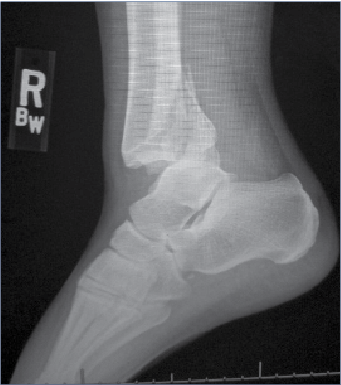

About 250,000 people in the United States have ankle fractures every year and 7% of those are open fractures, noted Jason St. John, DPM, MS, at yesterday’s APMA National session. He said fixation options for distal fibula fractures include lateral plates, posterior plates, intermetatarsal screws, intermetatarsal nails, lag screws, or external fixation. He said the approach can help dictate fibular fixation, and one should consider skin and bone quality.